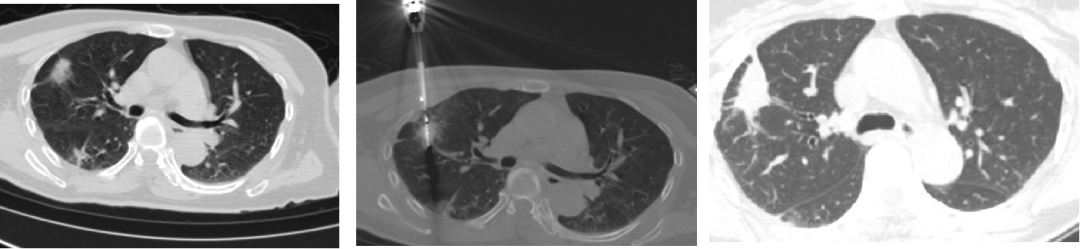

而直到今年8月,结节才终于做微波消融打掉,并取到了满意的病理:原位腺癌。

图2 张女士术前、消融中、消融后三个月复查结果